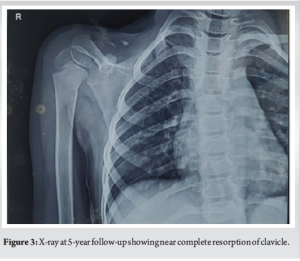

A 9-month-old infant presented to us with high-grade fever and pain in the region of the medial end of right clavicle (Fig. 1). Clinical examination revealed tenderness, swelling and discharging sinus over medial end of clavicle. Serological parameters and magnetic resonance imaging (MRI) were suggestive of medial clavicular osteomyelitis. The patient was operated on with incision, drainage of pus and wide local debridement for the osteomyelitis, and pus was sent for culture. The patient was given sensitive antibiotics for 6 weeks and the patient was kept on regular follow-up. There was complete resolution of infection at 6-week follow-up with no evidence of recurrence. The wound healed uneventfully and there was no clinical or serological evidence of infection. At sequential follow-ups of 1 and 5 years clavicle was not visualized (Fig. 2-4). At the latest 13-year follow-up, the patient has no evidence of right clavicle bone in comparison to the complete normal left clavicle (Fig. 5; 6a and b). But upon detailed clinical evaluation, the patient has no functional deficit (Fig. 7 and 8). He is able to attend school and carry out all his daily activities without any trouble whatsoever. Manual muscle testing grading showed near-normal power in all the muscle groups of the right upper limb. The DASH score in the right limb was 10 signifying better function. The grip strength of the right hand was not reduced as compared to the opposite normal side.

Hematogenous osteomyelitis of the clavicle is a rare entity with the incidence being around 1–3% [6,7]. Owing to the similarity of the clavicle to other membranous bones like ilium, osteomyelitis of clavicle is more difficult to treat than osteomyelitis of long bones [8]. The primary aim of management remains early diagnosis and prompt management with wide local debridement and appropriate sensitive intravenous antibiotics [1,9]. The known complications of clavicular osteomyelitis are sepsis, mediastinitis and hemorrhage from great vessels [10]. A rare and sparsely reported complication of osteomyelitis remains resorption of the bone. Bacterial infection of bone causes inflammatory bone loss that results from an imbalance between the increased activity of bone-resorbing osteoclasts, and a decrease in bone-forming osteoblasts [11]. In our case, it was noted at sequential follow-ups that the clavicle had not grown as much as the opposite side. There was definitive evidence of clavicular resorption at 1- and 5-year follow-ups. At sequential follow–up, the patient had no complaints of functional deficit. At final 13-year follow-up, we decided to go for a detailed evaluation of the status of the upper limb. Clinical examination revealed no functional deficit whatsoever. The patient has no difficulties in performing all the activities of daily living. He is able to attend school and play merrily. Objective evaluation with DASH score was around 10 pts (Range 0–150 with 0 being best function and 150 being poor function) and the grip strength by dynamometer showed no significant difference as compared to the normal opposite side. Upon imaging the X-ray, computed tomography and MRI revealed complete clavicular resorption. In this particular case, the patient has no clavicle at all! Yet he is able to perform all his activities smoothly and without any deficit.